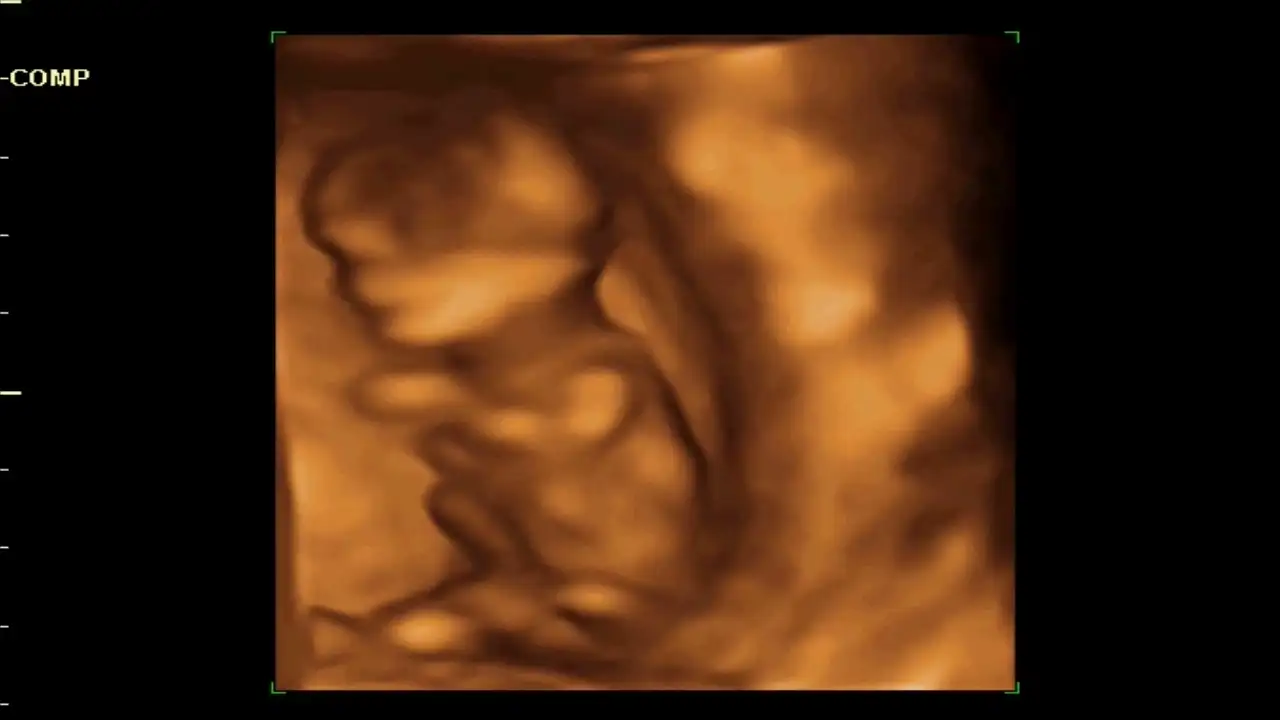

Kızlar merhaba, en son ikili tarama için doktora gittiğimde (12haftalikken) bana verilen 4 boyutlu görüntülerin resmini gönderiyorum sizlere.o gün doktor ile cinsiyet muhabbeti yaparken tahmin için çok erken olduğunu fakat pipi gibi bir çıkıntı görmediğini söyledi.6 Kasımda randevum var o zaman tam 16 haftanın başında olacağım umarım belli olur.ama meraklanmamak , hazırlıklara başlamak için sabirsizlanmamak elde değil :( sizlerden tahmin yürütebilecek var mı ?? :)